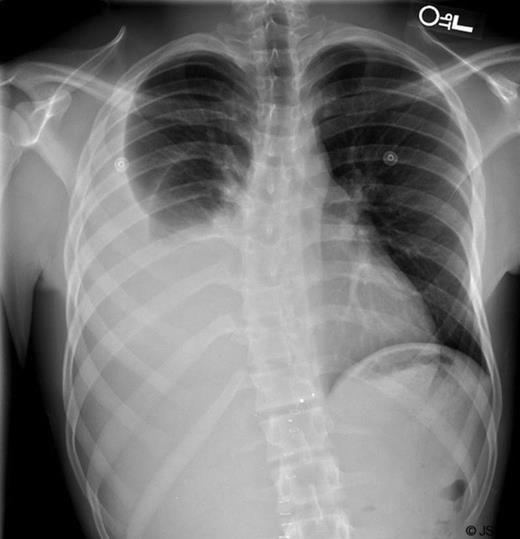

A few days later, the interventional radiologists attempted lymphangiography and embolization of the leaking duct (Figure 5). This also proved unsuccessful and did not improve the output. The patient was subsequently taken to the operating room for a re-exploration and attempted ligation of the lymphatic leak transabdominally. During surgery, the right crus was divided and the retroperitoneal tissues to the right of the supraceliac aorta were ligated in an attempt to obstruct the lymphatics draining proximal to the transhepatic injury. Following this operation, there was an immediate decrease in the output from the chest tube associated with an improved chest x-ray. The chest tube was removed on post-op day #7 once the patient tolerated a regular diet without any increase or change in output. The patient was discharged home the next day and has since recovered well from his injury.